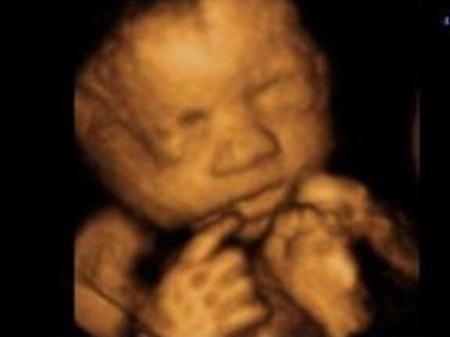

3.四维超声

根据超声方法监测胎儿生长发育情况,了解胎儿各器官构造及羊水、胎盘情况,筛查胎儿畸形。